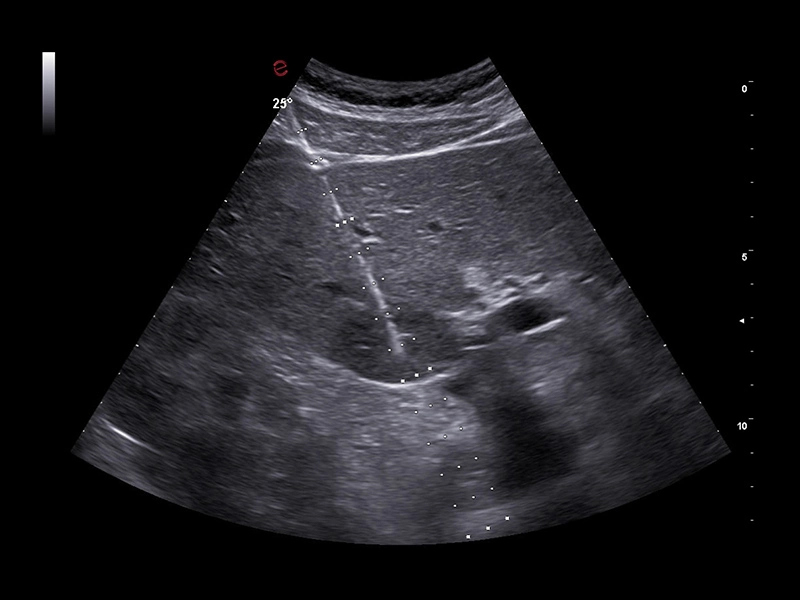

MyLab™X9 - Interventional

MyLab™X9 - Interventional